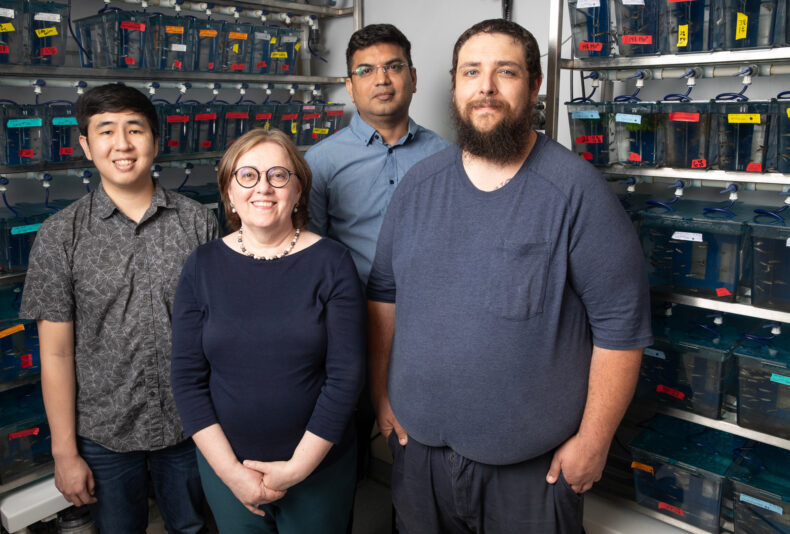

Ela Knapik, MD, associate professor of Medicine at Vanderbilt University Medical Center, and her colleagues discovered the syndrome caused by mutation of a single gene and named it CATIFA, an acronym for its core symptoms: cleft palate, cataracts, tooth abnormality, intellectual disability, facial dysmorphism and ADHD.

VUMC researchers joining Knapik, Gamazon and Cox on the study are first author Gokhan Unlu, PhD, Amy Rushing, B. Eng, Xinzi Qi, David Melville, PhD; VU researchers are Rui Chen, PhD, Bingshan Li, PhD; clinical collaborators in Saudi Arabia include Fowzan S. Alkuraya, MD, Nisha Patel, PhD, Mais Hashem, MS, and Abdullah Al-Faifi, MD. The research was supported by the National Institutes of Health (grants MH113362, HG009086, HG010718, GM008554).